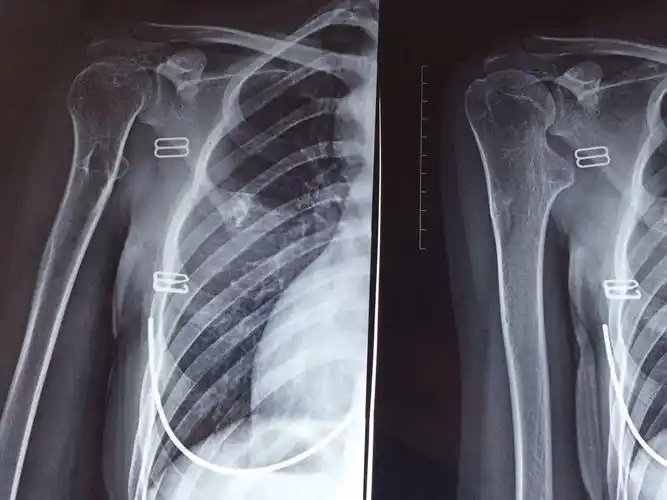

女24,年轻女性多关节多发骨疣怎样处理?